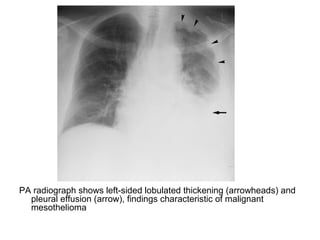

PA radiograph shows left-sided lobulated thickening (arrowheads) and

pleural effusion (arrow), findings characteristic of malignant

mesothelioma